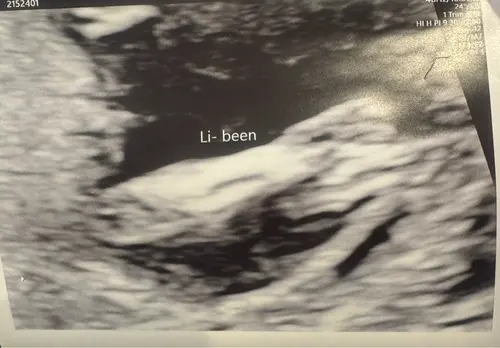

Is dit een jongen of een meisje??

Maar kan nog veranderen aangezien je nog 12+4 ben

🩵 of 🩷?

Ik denk dat je nog vroeg ben dan is alles nog meisje, mijn zwangerschap nu heeft tot ruim 13weken op meisje geleken terwijl toch jongen is want met 13+6 zagen we duidelijk zijn piemel.

Ah oké! Deze foto’s waren met 13+2